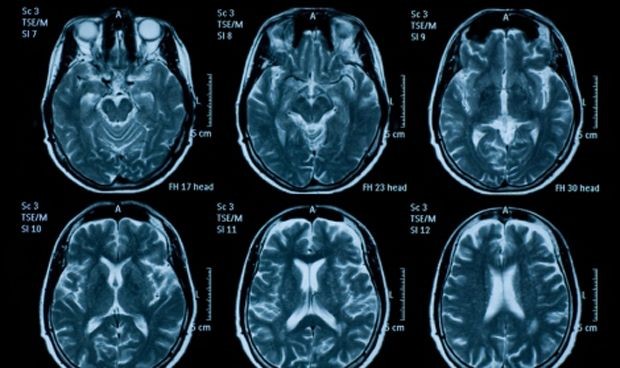

El ictus es una enfermedad cerebrovascular ocasionada por la falta de sangre necesaria al cerebro debido a la presencia de un trombo. Esta enfermedad es la primera causa de mortalidad entre las mujeres españolas y la segunda en los hombres y ocasiona un elevado gasto sanitario.